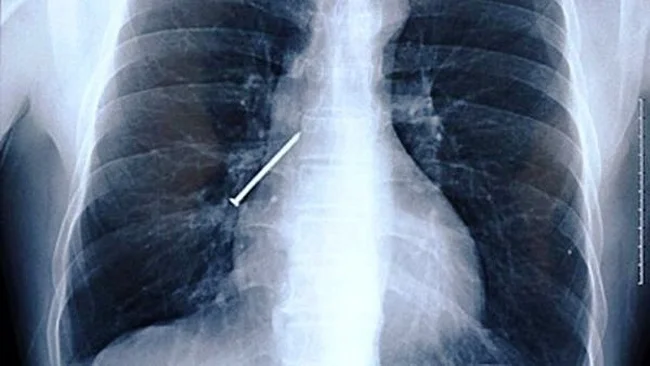

Не до жартів було жителю Британії, якої перекусив у кафе і виявив у курячому крильці цвях. Він негайно звернувся по медичну допомогу, і з'ясувалося, що ще один цвях чоловік встиг проковтнути. На щастя, все обійшлося без наслідків.